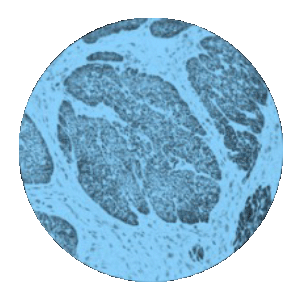

Mod-IHC.png

IHC/Biodistribution